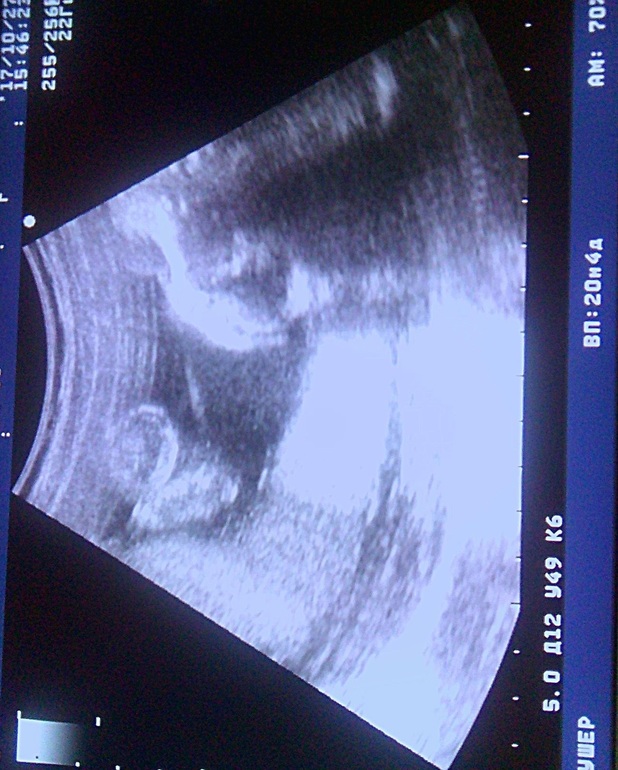

Дарья Бартенева → Новенькая Спам Мама девочки (13 лет) Новороссийск Девочки помогите понять по фото, это мужские половые органы? Читать далее